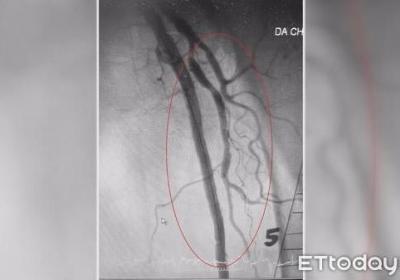

?腳也會中風!3高患者腿部動脈易阻塞 小心潰爛、發黑要截肢,?腳也會中風!3高患,者腿部動脈易阻塞 小,心潰爛、發黑要截肢...